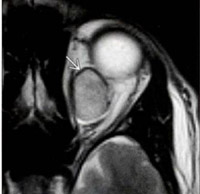

Los hemangiomas cavernosos son los tumores vasculares orbitarios más frecuentes en adultos, su síntoma principal es la proptosis de larga evolución, ya que son lesiones de crecimiento muy lento. Se pueden encontrar pliegues retinianos, compresión del nervio óptico, e hipertensión intraocular según el tamaño y la localización del mismo. El diagnóstico suele realizarse por TC. Se presenta como una masa intraconal ovoidea, bien delimitada, con captación intensa de contraste endovenoso (

Figura 5).

Figura 5. Hemangioma orbitario. RM secuencia T2SE axial. Masa intraconal de morfología ovoidea, bien definida. Muestra un halo hipointenso (flecha) que representa la pseudocápsula.